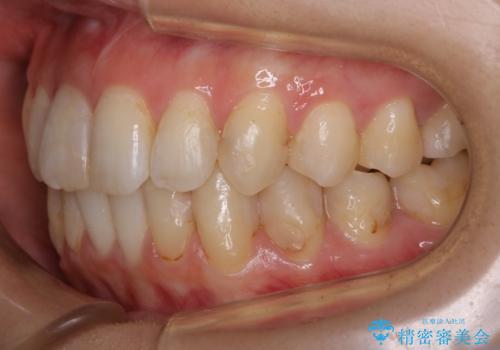

- 前歯のガタつきと噛み合わせの改善を希望してご来院されました。

目立たない装置での矯正治療をとのことでインビザラインを用いた非抜歯矯正を行うこととなりました。